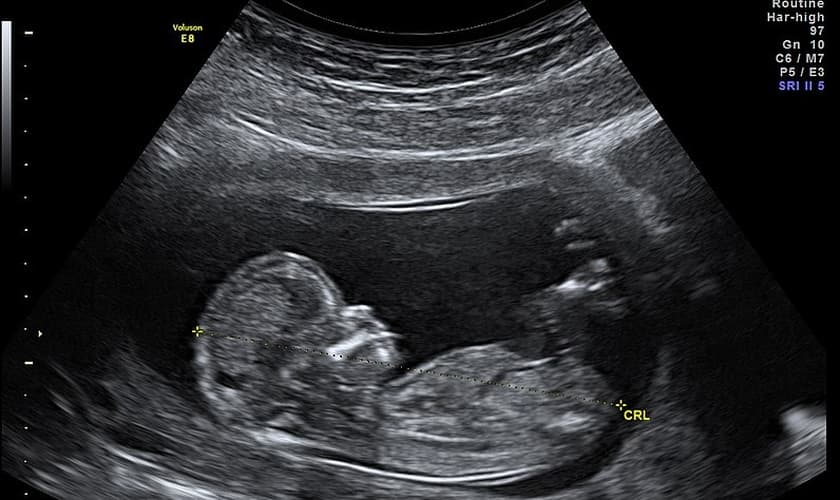

De acordo com a Rede, alguns médicos têm usado o cloreto de potássio para interromper gestações de mais de 20 semanas, apesar do manual de aborto do Ministério da Saúde não prever o método.

Segundo a Gazeta do Povo, todas os métodos de aborto causam dor ao naciturno, mas o uso do cloreto de potássio provoca sofrimento extremo ao bebê.